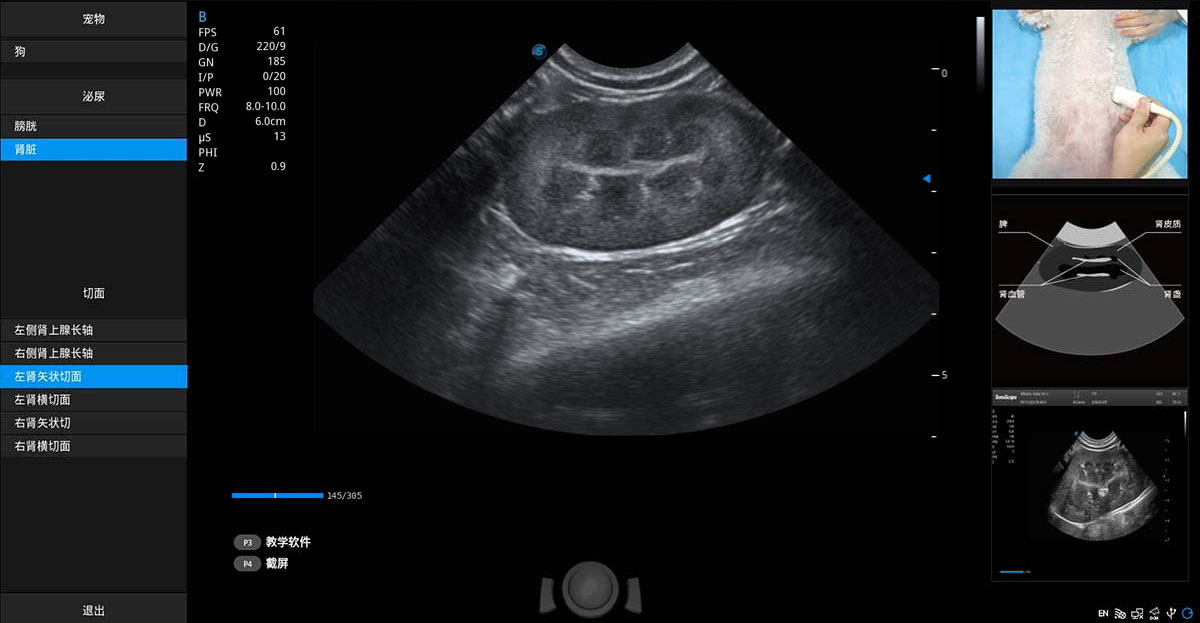

提供解剖示意圖、標(biāo)準(zhǔn)超聲圖像、掃查手法涂和操作者實(shí)時(shí)檢查圖像,指導(dǎo)操作者進(jìn)行標(biāo)準(zhǔn)切面的正確掃查。

ProPet 80 專為動(dòng)物醫(yī)生設(shè)計(jì),對(duì)不同的動(dòng)物體型和生理結(jié)構(gòu)作出了針對(duì)性的優(yōu)化。通過動(dòng)物影像專用軟件,可滿足個(gè)性化的應(yīng)用需求,幫助動(dòng)物醫(yī)生獲得更精確的診斷數(shù)據(jù)。

高性能和先進(jìn)的臨床應(yīng)用工具可以為動(dòng)物醫(yī)生提供臨床信心。ProPet 80 搭載了先進(jìn)的腹部和淺表應(yīng)用工具,幫助醫(yī)生在日常臨床實(shí)踐中發(fā)揮前所未有的作用。